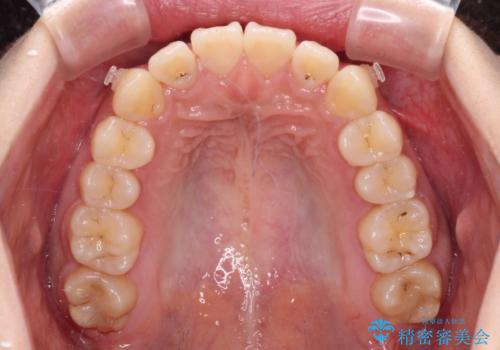

- 前歯の捻れを気にして来院された患者様です。

上顎前歯が捻れて前方に飛び出しており、下顎前歯もそれに沿うようにデコボコとなっていました。

IPR(歯と歯の間を削る処置)によりスペースを獲得して下顎前歯のデコボコを改善し、上顎前歯は下顎前歯と接する位置にまで引っ込めるように設定し、インビザラインにて矯正治療を行うこととしました。

しっかりと装着時間を守ってくださったので、予定通り1年強で治療を終えることができました。